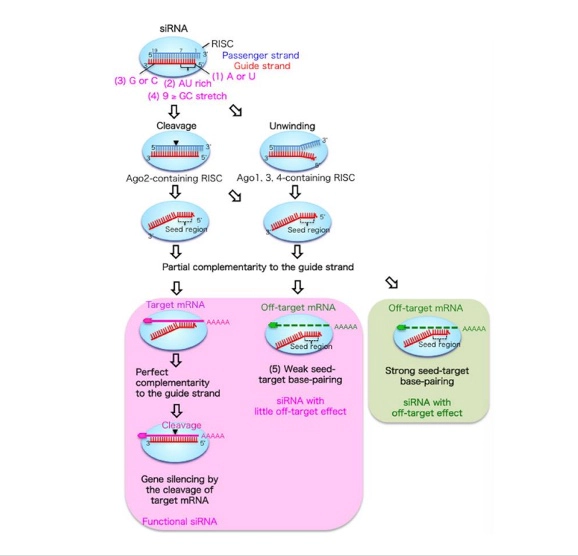

采用多维度策略评估 siRNA 的脱靶效应,包括依赖于杂交和不依赖于杂交的细胞反应和毒性机制。

杂交依赖性检测:

psiCHECK2 种子序列分析

Ago2 负载实验(评估 siRNA 是否成功进入 RISC 复合体)